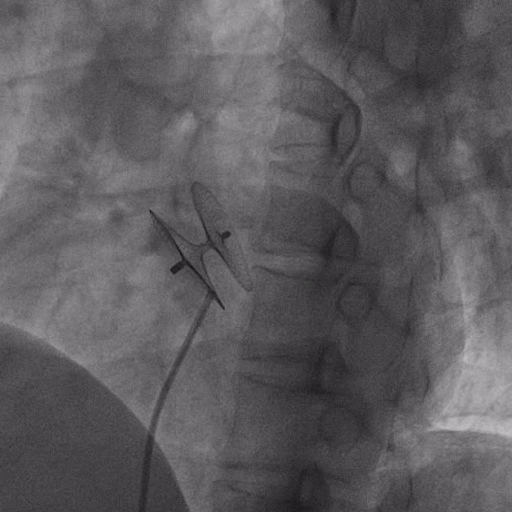

在獲得患者同意后,1月12日,尚福軍主任為患者進(jìn)行了PFO封堵術(shù)。術(shù)中造影可見封堵器殘余漏,尚福軍主任用精湛的技藝,順利通過封堵器殘余漏裂縫,將右心導(dǎo)管從右房送入左房,且順利到達(dá)肺靜脈;遂行卵圓孔未閉封堵術(shù)后殘余漏再次封堵;且完美釋放PFO封堵器,可見兩封堵器呈“馬蹄蓮”狀,再次術(shù)中造影未見殘余漏。

術(shù)后,小鞏生命體征平穩(wěn)。相關(guān)檢查顯示正常,且術(shù)后完善心臟彩超及發(fā)泡試驗,可見封堵器位置良好,未見右向左分流,發(fā)泡試驗陰性。